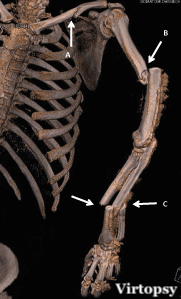

L'imagerie forensique est devenue, au fil des ans, une discipline très prisée des médecins légistes pour les assister dans leur discipline. Des reconstructions en trois dimensions d’images scanographiques acquises post-mortem permettent, par exemple, de reconstituer les trajets lésionnels provoqués par des balles, ce qui constitue un type de pièces à conviction à présenter devant une cour de justice.

Ce travail se base, en plus des données démographiques, sur les principales données recueillies à l’autopsie et au scanner, en aveugle l’un de l’autre, notamment le nombre de systèmes lésionnels, leur orientation, le calibre des projectiles et les résidus de tir, le bilan lésionnel détaillé ou la détection des épanchements. Sur le plan radiologique, les chercheurs ont établi un protocole d'acquisition précis comportant un topogramme de face en décubitus dorsal, les bras le long du corps, suivi d’une première acquisition cervico-crânienne sans injection de produit de contraste, reconstruites en traitements osseux et parenchymateux cérébral, puis d’une deuxième acquisition sans injection de produit de contraste, en coupes millimétriques, de la région cervicale à l’extrémité des pieds, reconstruites en traitements osseux, médiastinal et parenchymateux pulmonaires.

Une revue scanographique exhaustive de tous les organes traversés par le projectile

Les trajectoires balistiques sont ici évaluées au scanner dans les 3 plans de l’espace, selon la méthode utilisée par les médecins légistes dans les rapports d’autopsie, et d'après des éléments sémiologiques comme les défauts dans le revêtement cutané, associés à des bulles d’emphysème sous-cutanées par exemple. Le trajet hématique se manifeste, d'autre part, par une hyperdensité linéaire au sein des masses musculaires ou du parenchyme cérébral. Un trajet bulleux dans les organes pleins et les poumons sont également des critères d'évaluation précis, de même que le descriptif lésionnel de l’encéphale aux pieds, en analysant différents axes artériels et veineux (aorte thoracique et abdominale, troncs artériels supra-aortiques, mésentère, veine cave inférieure), ainsi que chaque organe, chaque segment osseux, avec latéralisation systématique et recherche d’épanchement au contact des organes pleins intra-abdominaux.

Les trajectoires balistiques sont ici évaluées au scanner dans les 3 plans de l’espace, selon la méthode utilisée par les médecins légistes dans les rapports d’autopsie, et d'après des éléments sémiologiques comme les défauts dans le revêtement cutané, associés à des bulles d’emphysème sous-cutanées par exemple. Le trajet hématique se manifeste, d'autre part, par une hyperdensité linéaire au sein des masses musculaires ou du parenchyme cérébral. Un trajet bulleux dans les organes pleins et les poumons sont également des critères d'évaluation précis, de même que le descriptif lésionnel de l’encéphale aux pieds, en analysant différents axes artériels et veineux (aorte thoracique et abdominale, troncs artériels supra-aortiques, mésentère, veine cave inférieure), ainsi que chaque organe, chaque segment osseux, avec latéralisation systématique et recherche d’épanchement au contact des organes pleins intra-abdominaux.

Une corrélation et une complémentarité significatives entre les deux techniques

Cette étude a inclus 225 cas, ce qui lui confère une solidité significative. Au final, et comme on pouvait s'y attendre, le scanner et l’autopsie semblent concordants dans bien des cas, notamment sur le nombre et l'orientation des systèmes lésionnels. L'autopsie semble supérieure sur les résidus de tirs cutanés tandis que le scanner l'emporte sur la détection des épanchements. Reste que, dans cette pratique, il existe des limites à l'utilisation du scanner, notamment pour identifier précisément le calibre des projectiles ou lorsque les membres se trouvent en dehors du champ d’acquisition. Cette étude, qui est soumise pour publication dans l'International Journal of Legal Medicine, permet d'établir une complémentarité suffisante entre le scanner et l'autopsie classique dans les cas de traumatismes balistiques fatals.